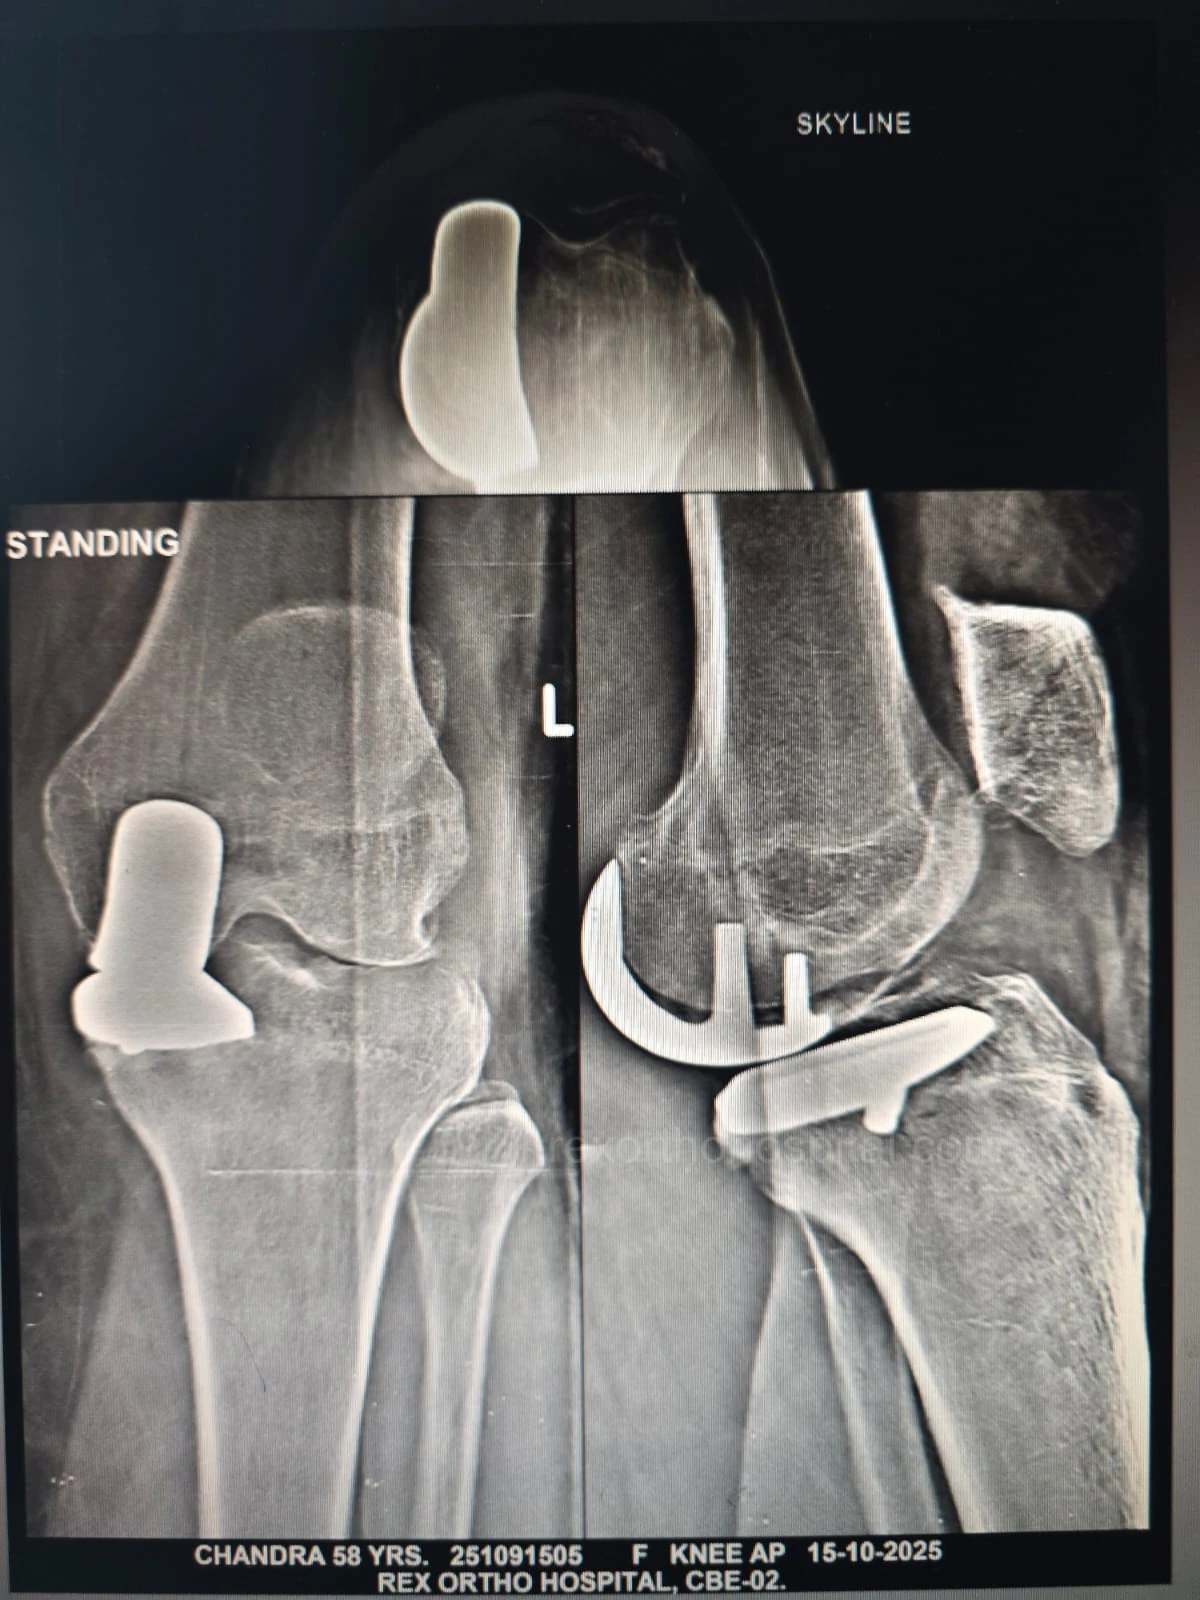

From diagnosis to surgery and recovery, our team ensures you receive expert treatment and individual attention throughout your treatment journey